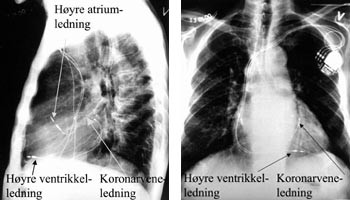

Terskelen for stimulering må kontrolleres også etter at introduserhylsen er fjernet og ledningen er fiksert, fordi ledningen lett kan dras ut av posisjon pga. den kraftige medstrømmen som er i sinus coronarius når man skal fjerne den 45 cm lange innføringshylsen. Deretter innføres en standard bipolar pacemakerledning via introduser i v. cephalica til apeks av høyre ventrikkel. Dersom pasienten har sinusrytme, innføres også en standard bipolar atriepacemakerledning via ny introduser i v. cephalica til høyre atriumsaurikkel (fig 2). Etter at høyre ventrikkel-ledningen er plassert, avledes elektrogrammet fra høyre ventrikkel og epikardialt fra venstre ventrikkel via pacemakerelektroden i kornarvenen simultant både på EKG-skriver og med pacingsystemanalysator (Medtronic analyzer 8090TM). Med skriverhastighet 100 mm/s måler man den interventrikulære ledningstiden ut fra elektrogrammene fra høyre ventrikkel og fra venstre ventrikkel (fig 3). Det bør være lengst mulig spredning i tid mellom ventriklenes spontane aktiveringselektrogrammer for at man ved pacing skal få best mulig resynkronisering av høyre og venstre ventrikkel. Tersklene for stimulering, P-bølgeamplituden og R-bølgeamplituden måles i henholdsvis høyre aurikkel og høyre ventrikkel med pacingsystemanalysator. Til slutt kobles alle ledningene til pulsgeneratoren InSyncTM som plasseres i pacemakerlommen.